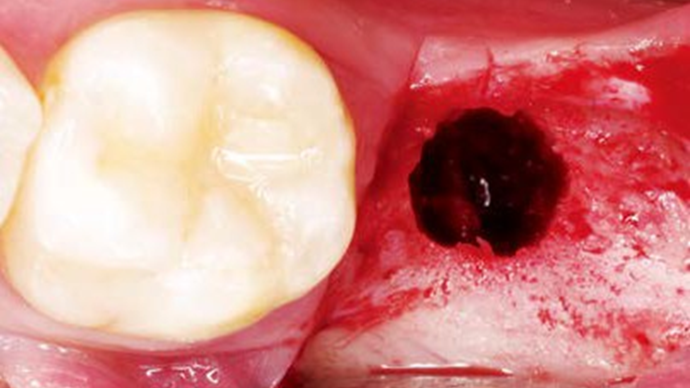

Clinical case: Bone filling into the bottom of deepest thread at 8.0mm AnyRidge fixture

- Courtesy of Dr. Kwang Bum Park -

Keywords

AnyRidge, Knifethread ,extraction socket, ,initial stability ,Allograft, ,osseointegratio ,Dr. Kwang Bum Park, , Mandibular, Single replacement, AnyRidge, Mega-oss,

Products used

Implant system-AnyRidge, Regeneration-Mega-Oss

How can primary stability be increased?

Primary stability is especially important in the case of poor quality bone. The instability of dental implants results in fibrous encapsulation and failed osseointegration (Lioubavina-Hack, et al. 2006). One method for increasing primary stability is modifying the surgical technique for implant placement. Studies have reported that the undersized surgical technique, which uses a final drill diameter smaller than the diameter of the implant, results in a higher primary stability when compared with the press-fit technique (Tabassum, et al. 2009, Tabassum, et al. 2010a).

Ti implants with a deeper thread depth provide a higher surface area, which is advantageous for increasing stability in areas of poor quality bone (Abuhussein, et al. 2010). Ti implants with deeper thread depths also facilitate an increased load and mechanical interlocking with poor quality bone.

Another method increasing the primary stability is to change the implant design, such as the shape of the implant body and thread, length, and diameter. Various thread designs for taper implants and other dental implant designs have already been reported to effect the primary stability. Taper implants also show a higher primary stability than cylindrical implants (Kim, et al. 2009, Sakoh, et al. 2006, Wilmes, et al. 2008).